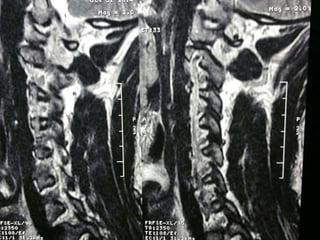

47 year old woman with 6 month h/o neck stiffness and pain with

left UE paresthesias into

The elbow forearm and hand especially IF/thumb

Note:the black line directly posterior to the vertebral bodies and relative

Thinning of spinal cord, note normal disc height